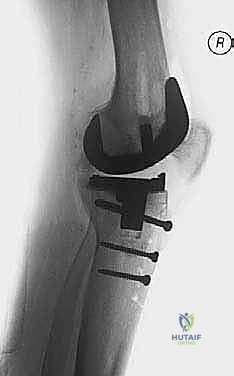

The structural allograft is temporarily secured to the host tibia using Kirschner wires. The allograft host construct is then reamed as a single unit to accept the diaphyseal stem. Definitive fixation of the structural allograft to the host bone is typically achieved with interfragmentary lag screws or by the press fit interference of the diaphyseal stem passing through both the graft and the host diaphysis.

Zonal Fixation and Stem Implantation

Regardless of the grafting technique utilized, the definitive implant must achieve rigid stability. Diaphyseal engaging stems are mandatory when massive bone grafting is performed. The stem must bypass the grafted area by a minimum of two cortical diameters into the intact diaphysis.

Cementless, fluted, tapered stems are widely favored as they provide excellent rotational stability and immediate rigid fixation in the diaphysis. The metaphyseal portion of the implant, resting on the bone graft, is typically cemented. Care must be taken to prevent cement extrusion between the structural allograft and the host bone interface, as this will mechanically block biological incorporation and lead to graft nonunion. Offset stems may be required to accommodate the mismatch between the center of the diaphyseal canal and the center of the tibial plateau, ensuring optimal coverage of the reconstructed metaphysis.